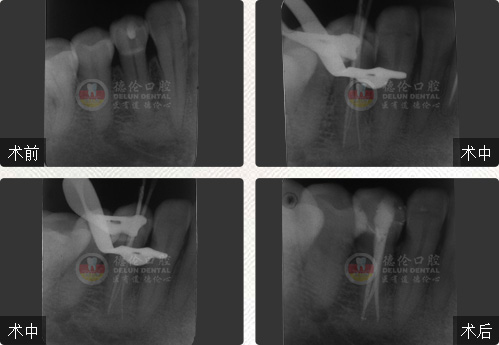

• 性別:

年齡:55歲

牙齒癥狀:急性牙髓炎(左下牙自發性、陣發性痛3天)

治療方法:顯微根管治療

疑難點評:操作方面使用根管顯微鏡和超聲波系統細致尋找和定位根管,根管的敞開度較為完美,維持了根管的原有走向,充填致密,流暢,充填長度準確。